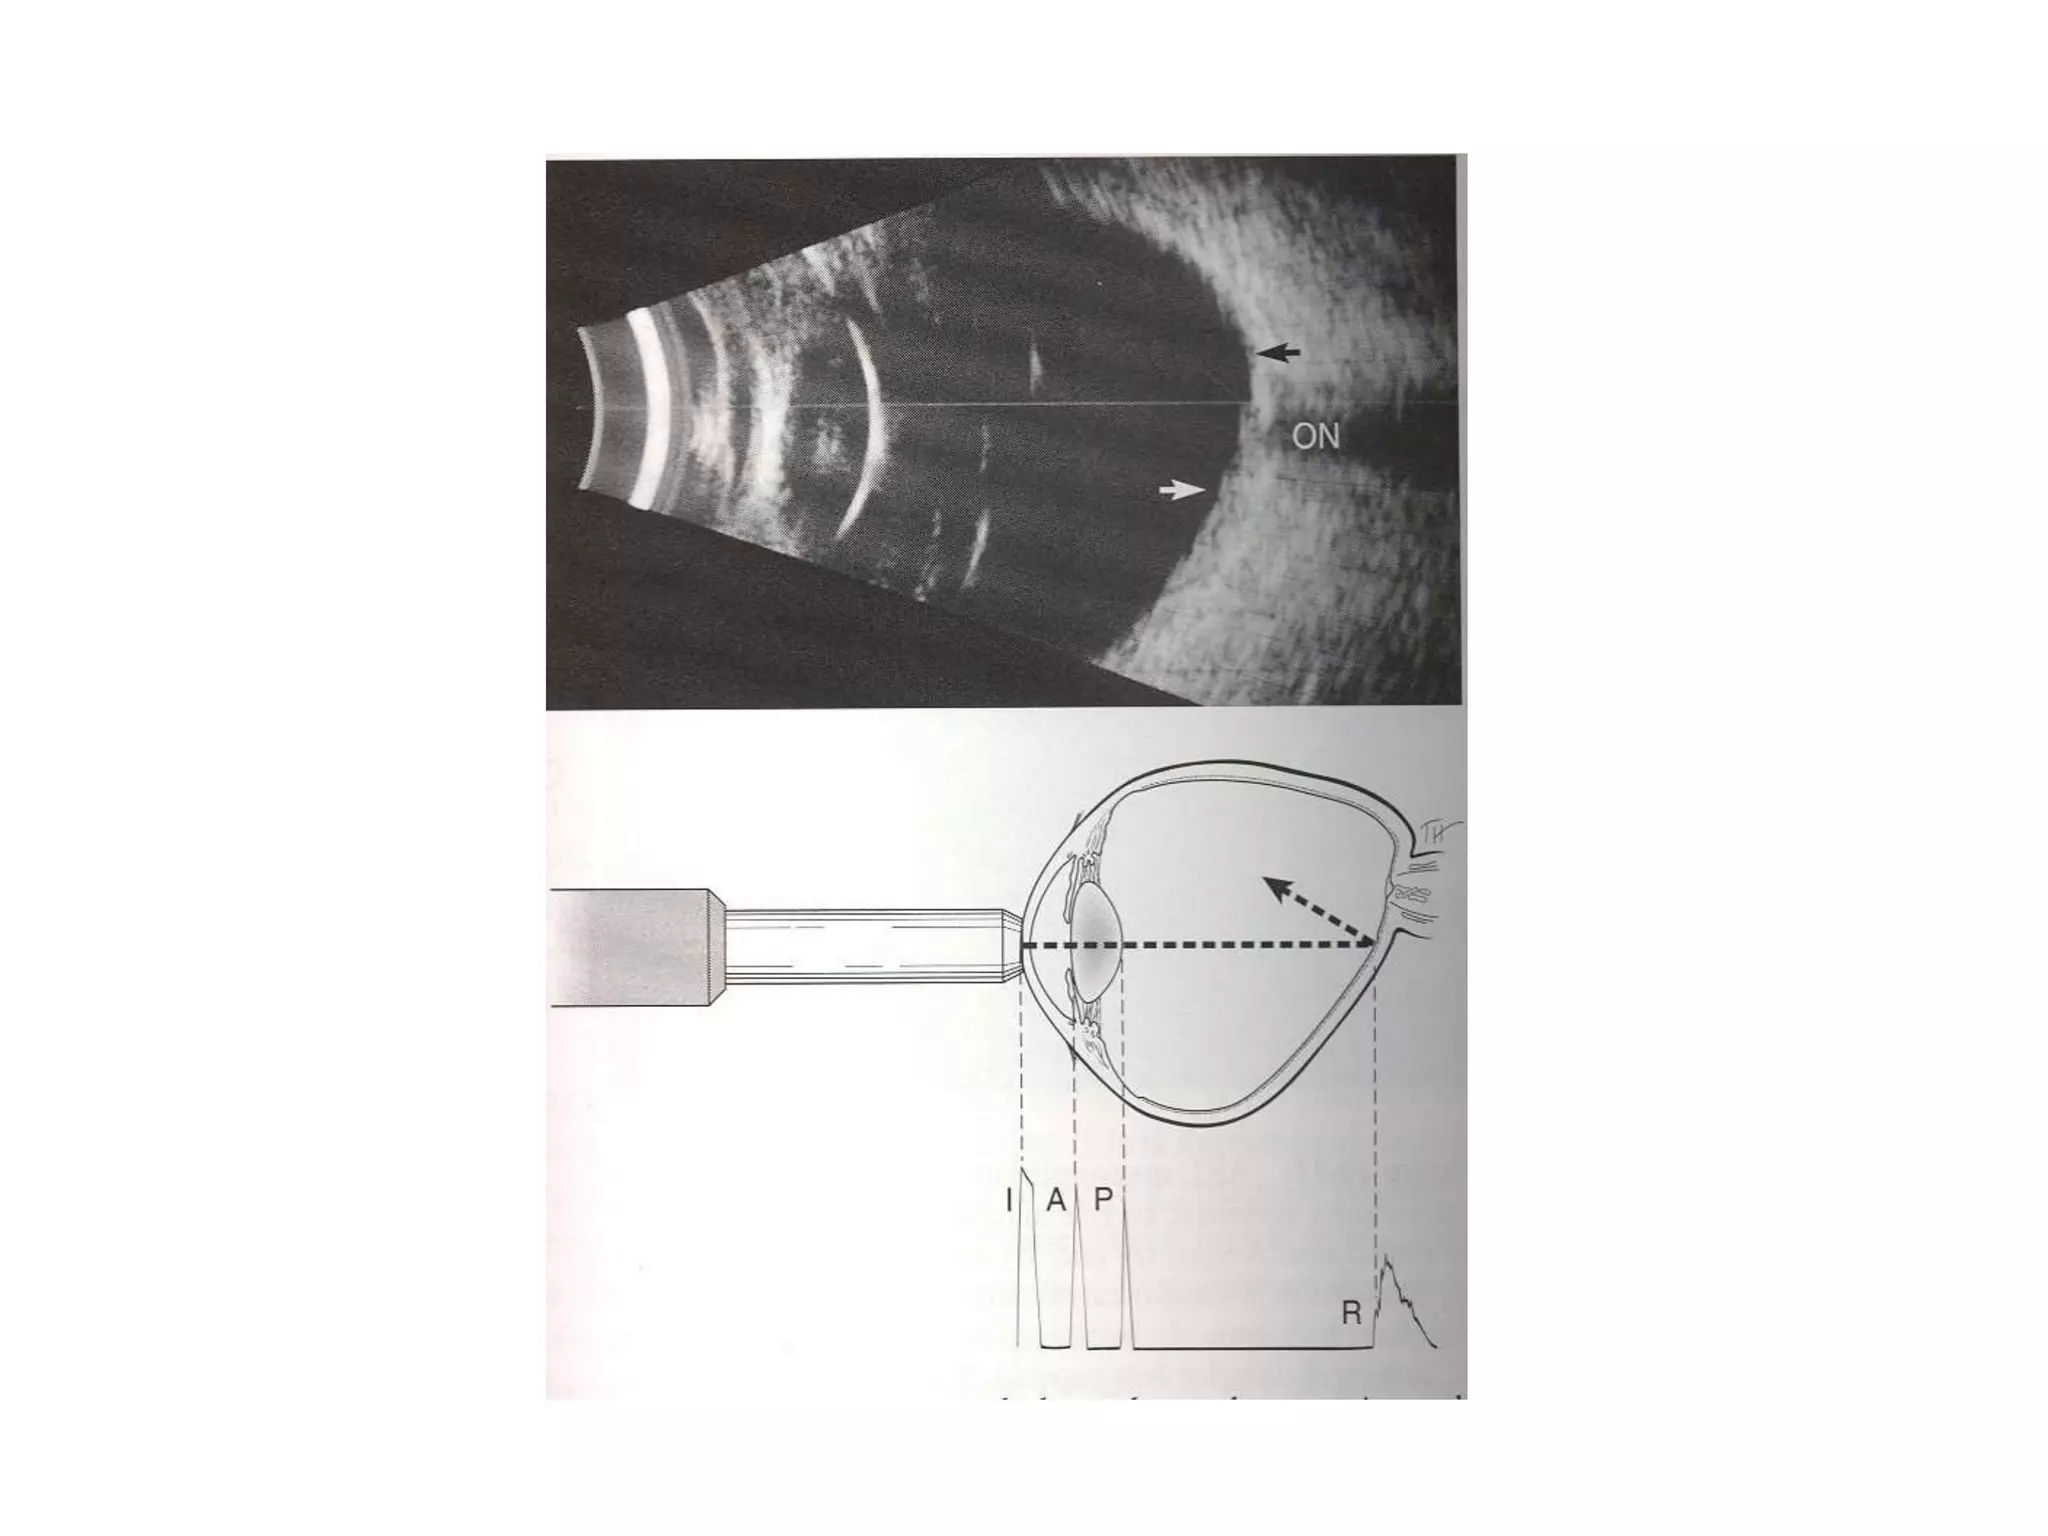

Ultrasound biometry

Ultrasound is

produced in the

ultrasonographic

probe by the

oscillation of a

pizoelectric

crystal

Converting

electrical energy

into mechanical

energy

The probe emits

and receives

pulsed signal

Reflectivity vs

time is displayed

for the single

direction in which

the probe is

pointing

This value then

be converted to

milimitres

C A P + R S